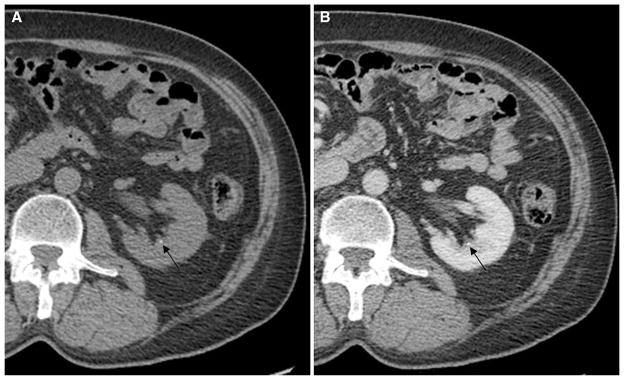

For the three reviewers, there was a combined total of 135 stones which were not detected, out of a maximum combined total of 714 stones. The mean diameter (±SD) of these undetected stones was 2.1 ± 0.75 mm with a range of 1–5 mm. Figure 2 provides an example of a 3-mm stone that was not detected on postcontrast images by one of the three reviewers. There was also a combined total of 10 false-positive stones, with a mean recorded diameter (±SD) of 1.5 ± 0.66 mm and a range of 1–2.9 mm.

Fig. 2.

A 47-year-old man with bilateral flank pain. Non-contrast (A) and postcontrast (B) CT images demonstrate a 3-mm non-obstructing calyceal stone in the left kidney. This stone was not detected on the postcontrast series of images by one of the three reviewers.